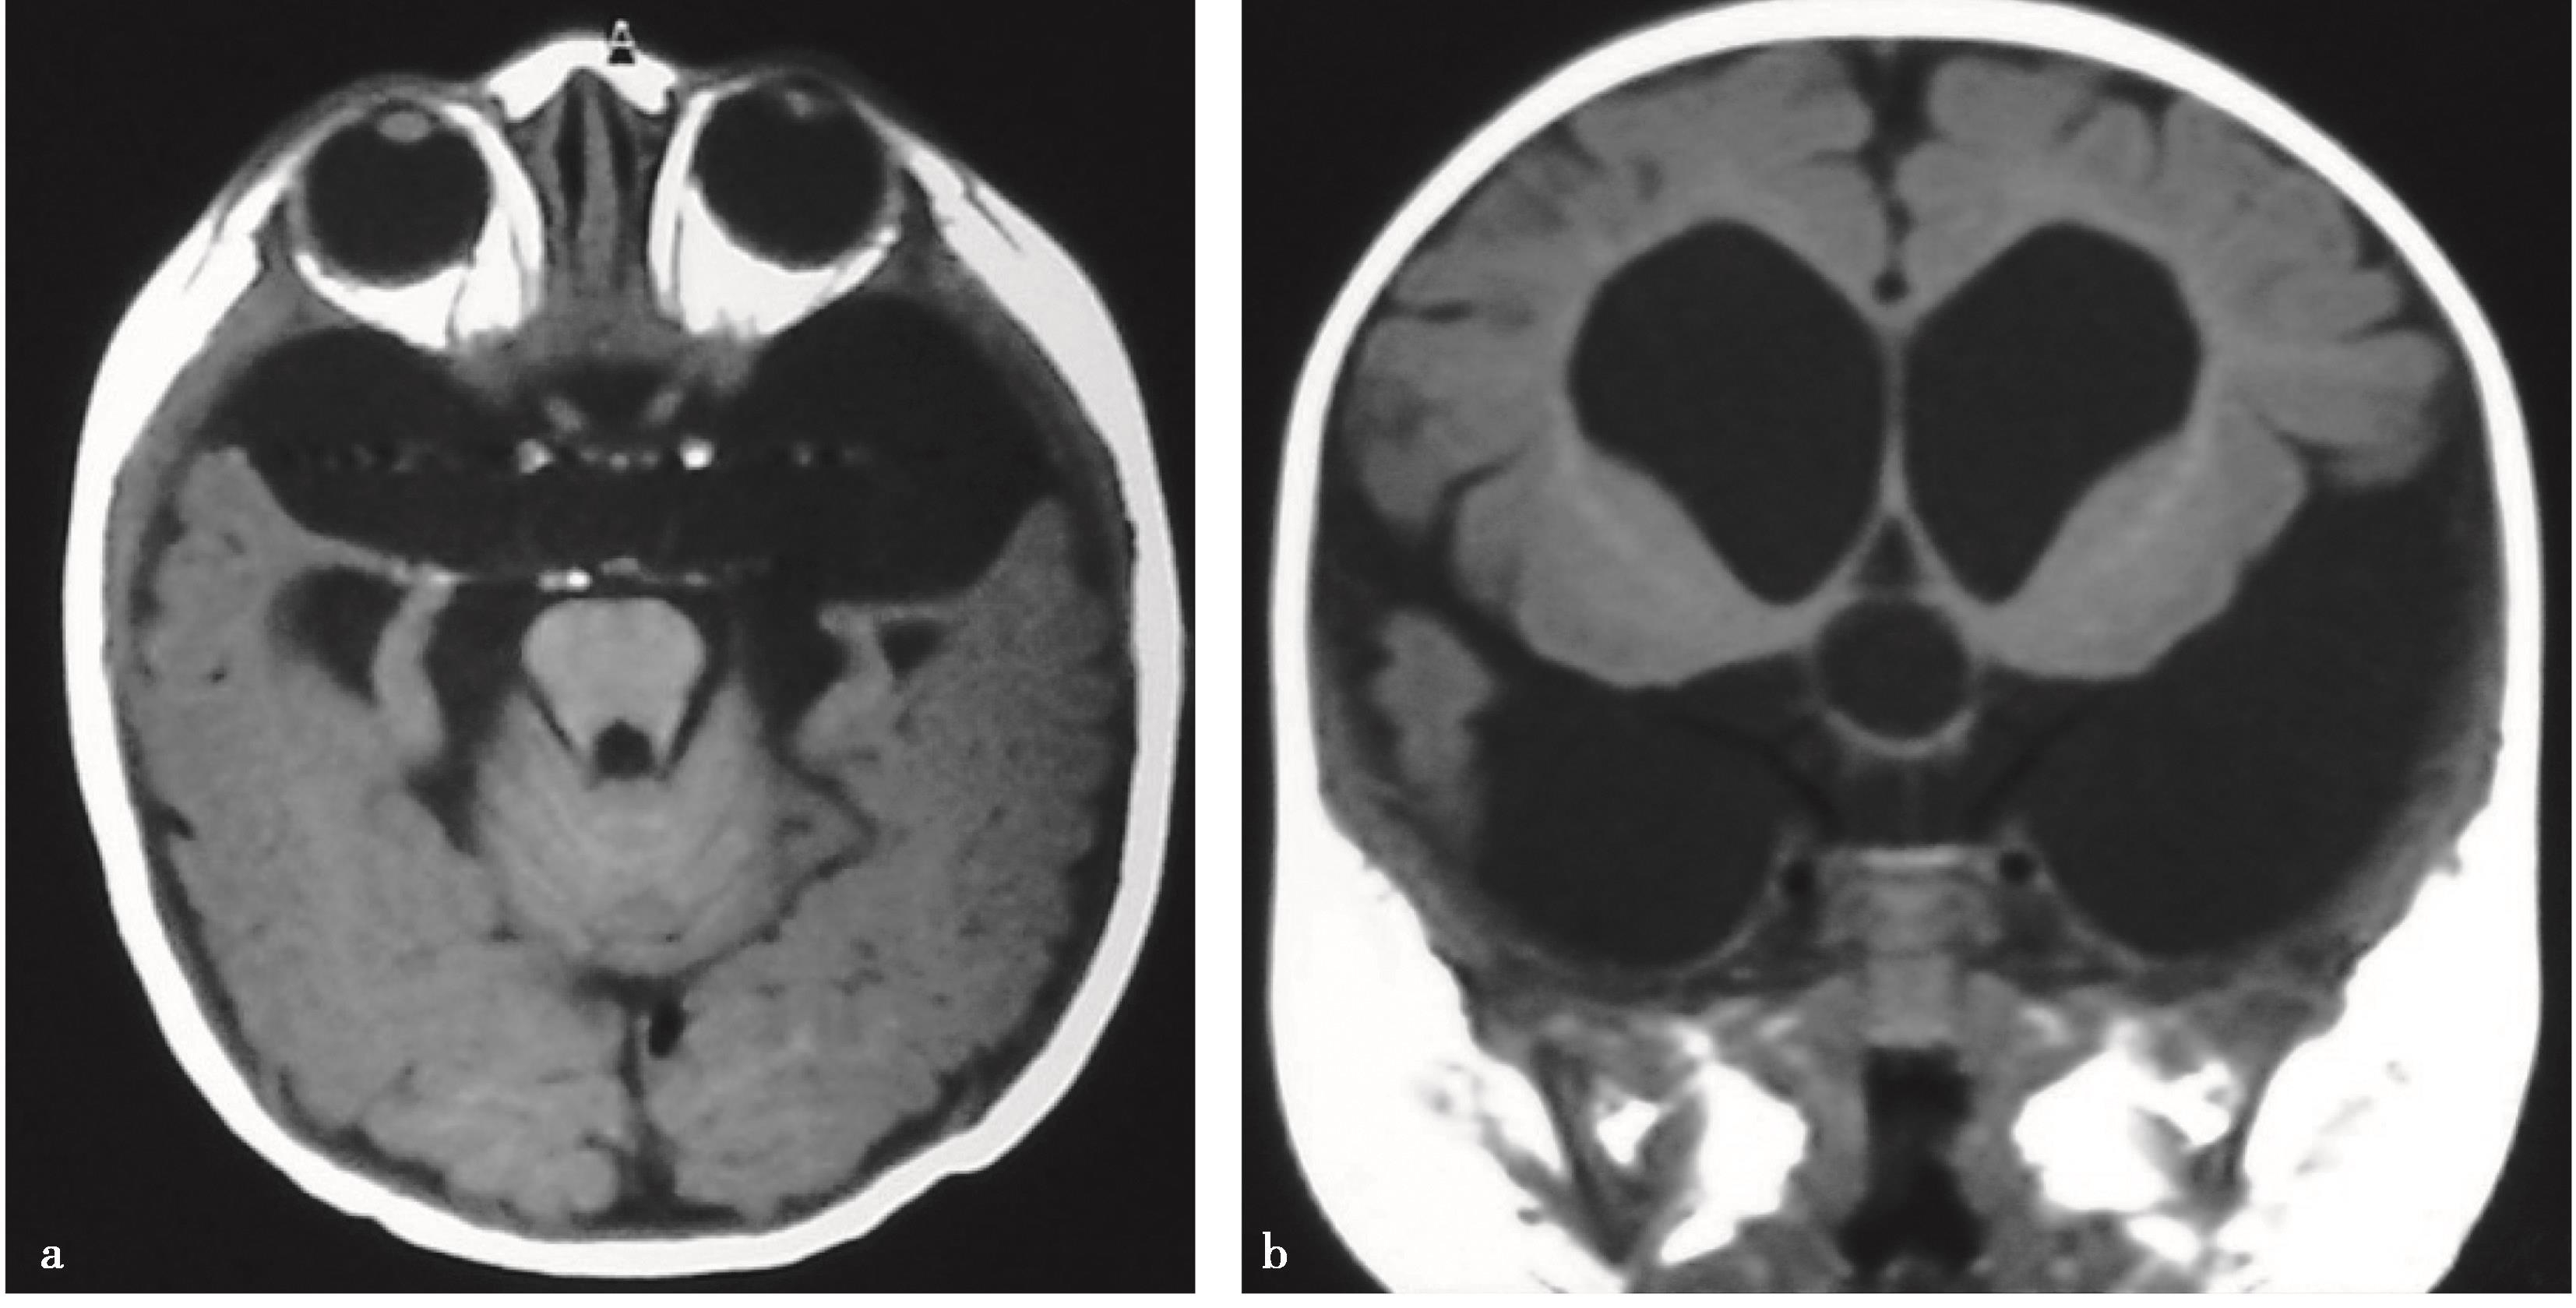

2.单侧或双侧室间孔狭窄或闭塞所致一侧或双侧侧脑室积水,采用内镜下室间孔成形术进行治疗(图3-1-2-1)。

图3-1-2-1 室间孔狭窄的影像学表现

a.右侧室间孔狭窄,头颅MRI轴位;b.右侧室间孔狭窄,头颅MRI冠状位;c.左侧室间孔狭窄,头颅MRI轴位;d.双侧室间孔狭窄,头颅MRI冠状位;e.内镜下可见左侧室间孔闭塞、右侧室间孔狭窄;f.内镜下可见左侧室间孔闭塞;g.内镜下可见右侧室间孔闭塞;h.室间孔球囊成形;i.经球囊成形后的室间孔